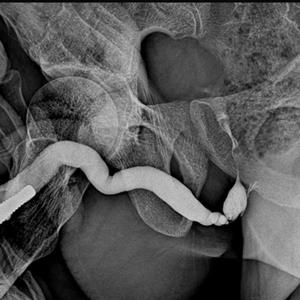

RGU :: RETROGRADE URETHROGRAM

IT IS DYE STUDY OF WHOLE URETHRA IN 2 TO 3  LIVE X.RAYS